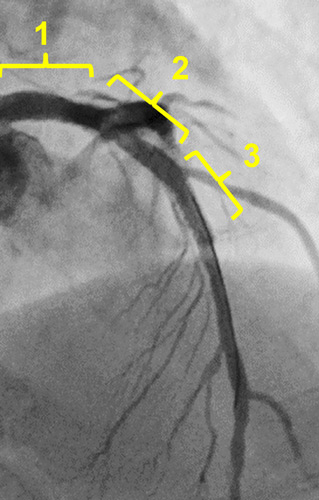

Blood pressure was correct. Non compliant balloon inflation, no extravasation.

One stent strategy

Final angiography

The final IVUS showed stent was apposed correctly and fully expanded.